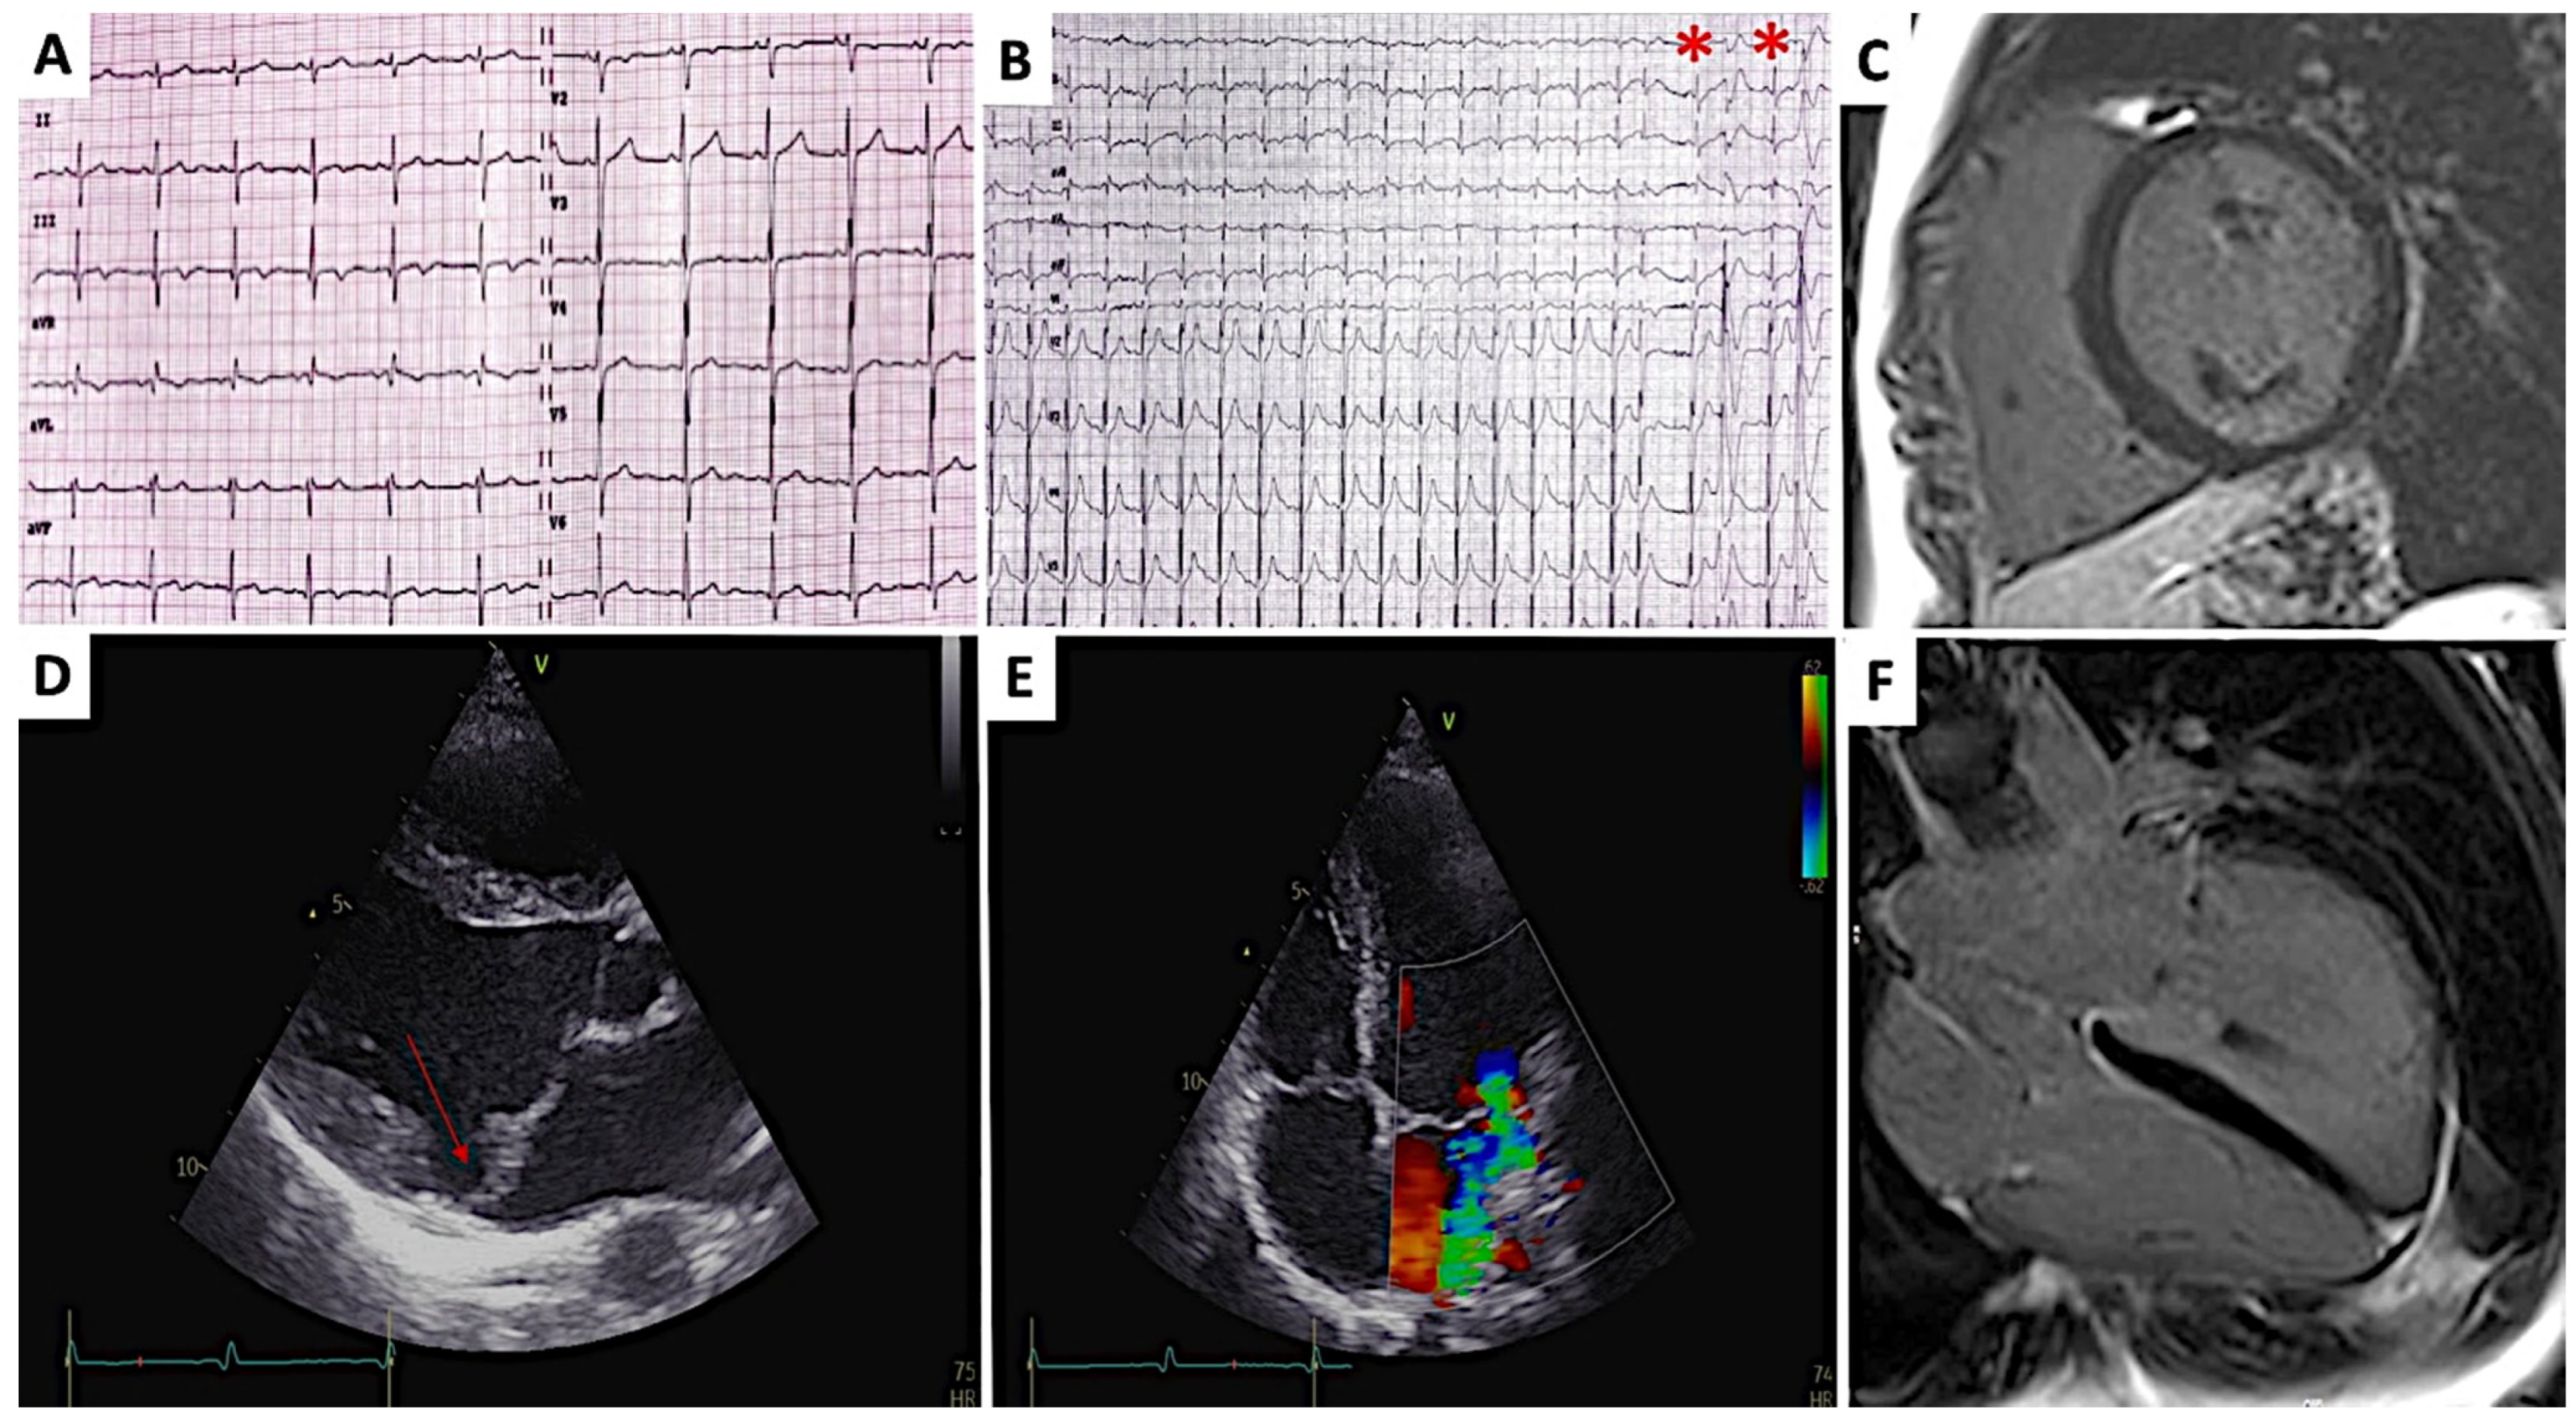

Arrhythmic Mitral Valve Prolapse in the Young: A Rare but Concerning Entity